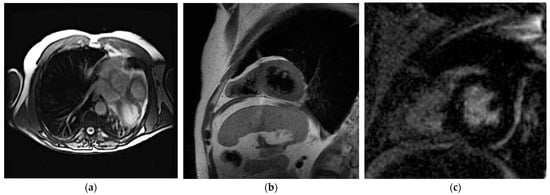

7.3. Cardiac Magnetic Resonance Imaging

| CMR | Direct pericardium visualization Evaluation of heart position Evaluation of heart function | Temporal resolution Tissue characterization | Long acquisition time Claustrophobia Presence of devices (compatibility, artifacts) High cost |